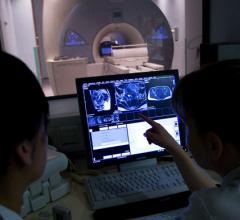

Radiology departments have many different needs and face a wide variety of challenges that can impact their departments ...

The pressure to be efficient and effective when imaging outpatients may be rising due to imaging’s increased presence ...

Bayer Radiology’s Barbara Ruhland and Thom Kinst discuss how radiology departments can address the many different ...